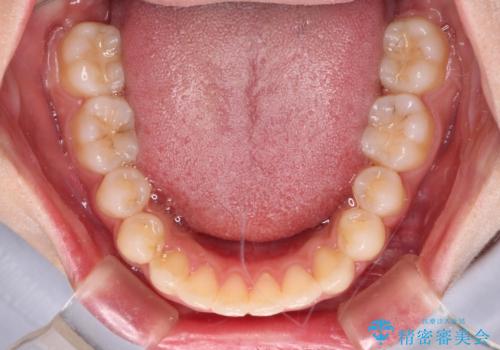

レントゲン写真上では、矯正治療前後で歯根長さに大きな違いはなく、抜歯を回避することができました。

上顎内側に転位している前から2番目の歯は移動が難しく、無理矢理歯根全体を動かそうと設計すると、歯肉退縮・歯髄壊死・歯根吸収といった危険性が増すため、無難なゴールにて治療を終えることとなりました。